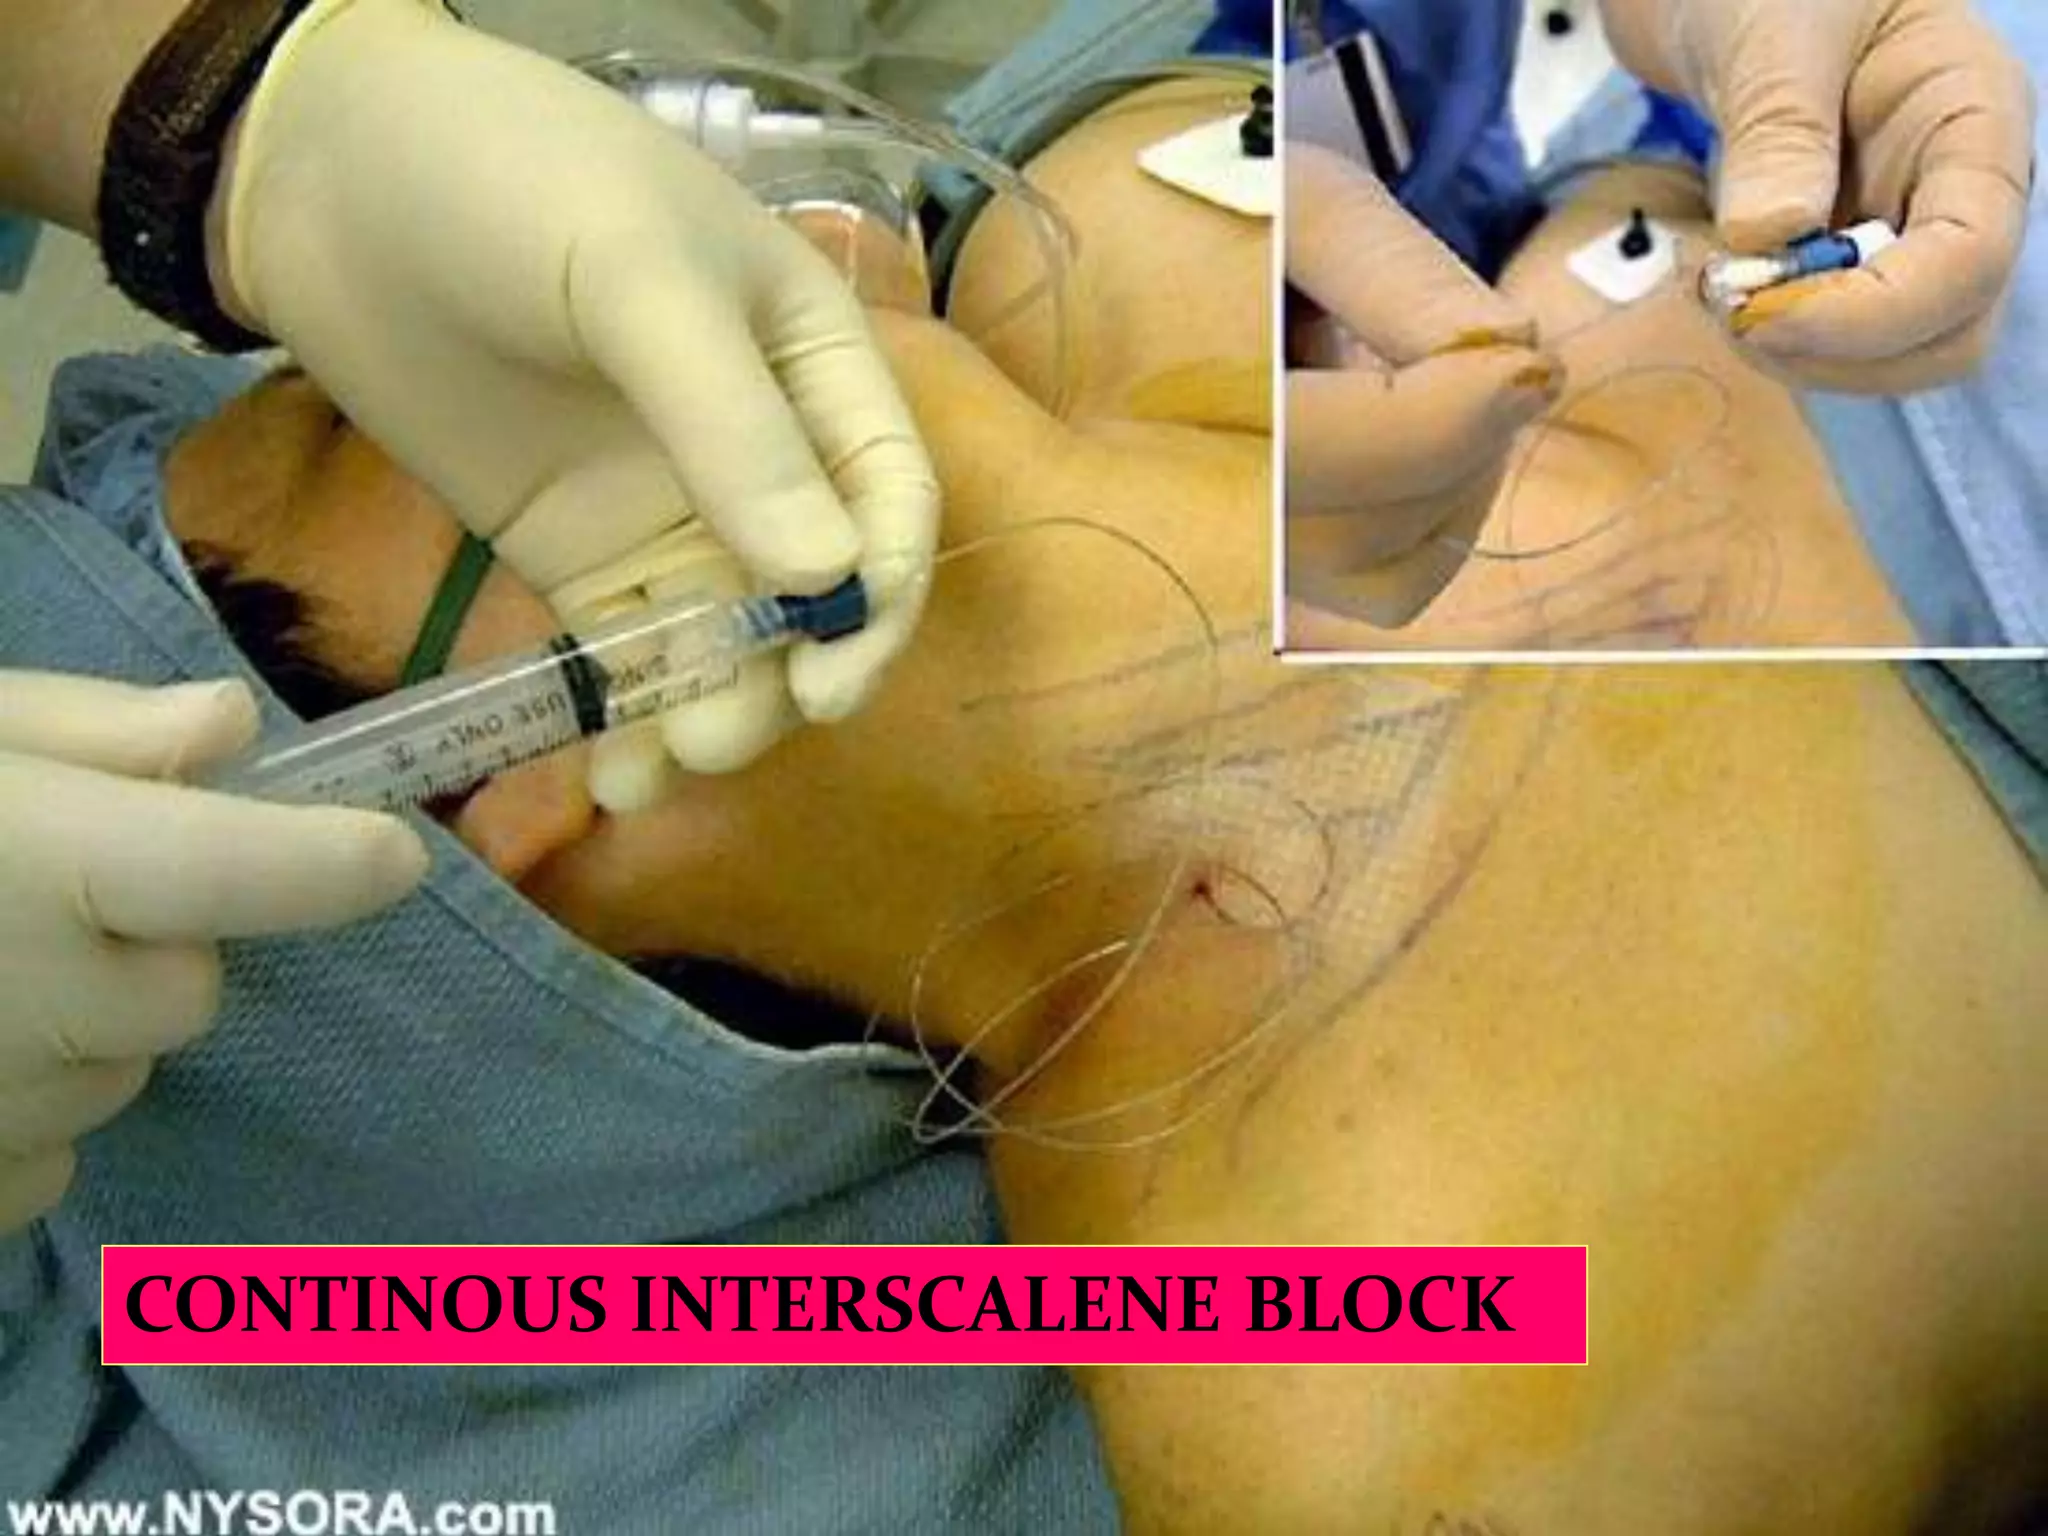

This document provides an overview of brachial plexus anatomy and techniques for brachial plexus nerve blocks. It begins with a description of the brachial plexus formation from cervical and thoracic nerve roots and its branching pattern. Four main approaches for brachial plexus nerve blocks are described: interscalene, supraclavicular, infraclavicular, and axillary. Details are provided on the anatomy and techniques for performing interscalene and supraclavicular brachial plexus blocks. Ultrasound guidance is discussed as an advancement which allows real-time visualization of needle and nerve. Complications are also summarized.